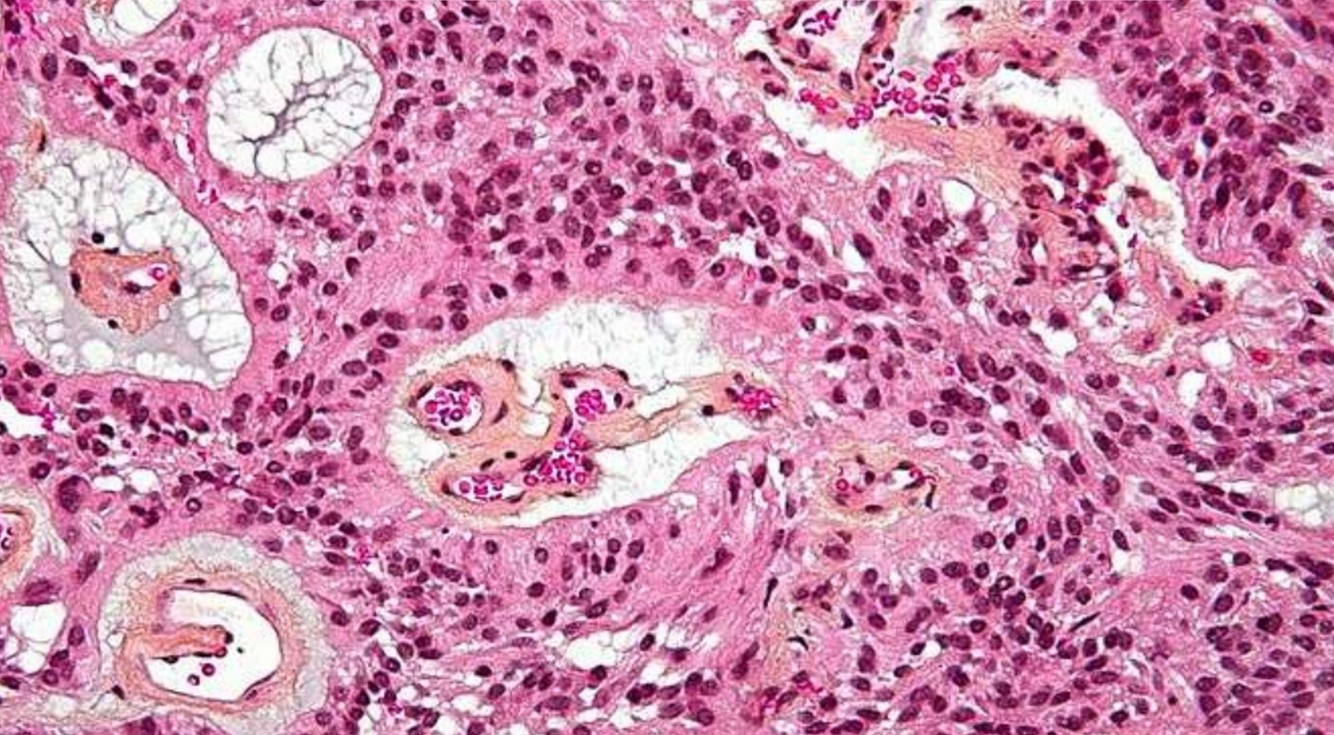

Ependymoma

- Incidence: 5% to 10% of primary brain tumors in the 1st two decades

- Arise around ventricular lining

- Locations:

- The 4th ventrical: common in children

- Spinal: adults, mean 40 yrs, NF2

- Loss/mutation of NF2 on chromosome 22q in spinal cord tumors